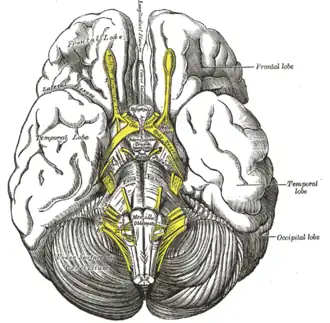

Tuber cinereum hamartoma is a benign tumor in which a disorganized collection of neurons and glia accumulate at the tuber cinereum of the hypothalamus on the floor of the third ventricle. It is a congenital malformation, included on the spectrum of gray matter heterotopias. Formation occurs during embryogenesis, typically between days 33 and 41 of gestation. Size of the tumor varies from one to three centimeters in diameter, with the mean being closer to the low end of this range. It is estimated to occur at a frequency of one in one million individuals.[1]

Anatomic and imaging findings

The tumor is difficult to detect by CT due to decreased sensitivity of the scan at the level of the sella turcica. MRI is the primary imaging modality for detection, with the lesion being of similar signal intensity to gray matter and non-enhancing with contrast. Lack of enhancement is an important imaging characteristic to help distinguish the tumor from similar masses that can occur in this region. These include germ cell tumors, granulomas of Langerhans cell histiocytosis and hypothalamic astrocytomas, as these lesions usually demonstrate at least partial uptake of contrast.[1]